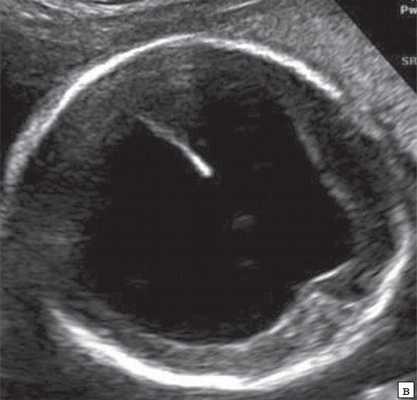

Анализ сохраненных трехмерных изображений позволил получить более детальные характеристики структур мозга плодов с РЭС. На среднесагиттальном срезе в наблюдениях 1, 2 и 4 (в наблюдении 3 получить качественно этот срез не удалось) отмечено наличие атипичной полукруглой формы шатра (fastigium) 4-го желудочка, гипоэхогенная структура мозжечка с контрастирующим наружным контуром (рис. 3). При этом в первых трех наблюдениях отмечено полное отсутствие структур червя, тогда как в наблюдении 4 по контуру 4-го желудочка выявлены гиперэхогенные структуры, расцененные как передние отделы червя. Наличие передних отделов червя отражает и ряд послойных срезов в режиме TUI (рис. 4). У плода в наблюдении 4 также обращает на себя внимание относительное расширение надмозжечковой цистерны, с линейными структурами, при нормальной ориентации намета мозжечка (рис. 4).

На эхограмме: М - мозжечок, 4v - четвертый желудочек, короткие стрелки - фрагменты червя.

При частичном РЭС в наблюдении 4 картины желудочковой системы (затылочные рога боковых желудочков - 7 и 7,9 мм, 3-й желудочек - до 2 мм), комплекса "полость прозрачной перегородки (ППП - 3,4 мм) - мозолистое тело (20,8 мм)", борозд мозга (глубина сильвиевой борозды - 7 мм), длины крыши четверохолмия (8,3 мм), водопровода, передне-задних диаметров мезенцефалона (11 мм) и моста (7,9 мм) соответствовали норме (рис. 6).

На эхограмме: М - мозжечок, Ц - цистерна, стрелка короткая - намет мозжечка, стрелка длинная - 4-й желудочек.